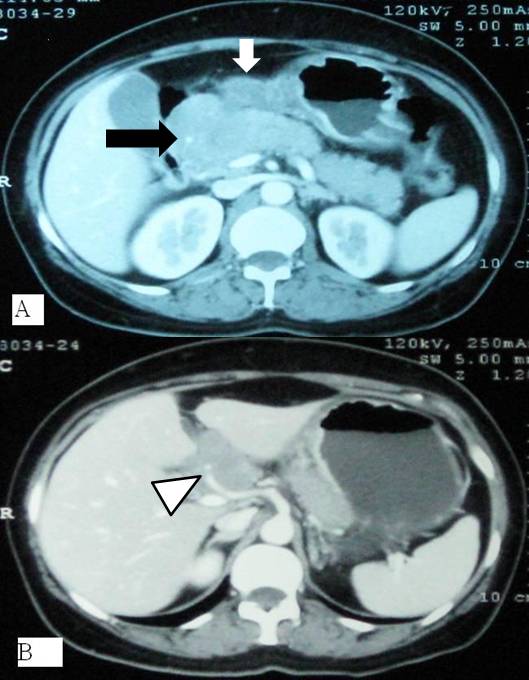

Context Diffuse large B-cell lymphoma is the commonest form of non-Hodgkin lymphoma. Gastro-intestinal tract and bone marrow are common extra-nodal sites of lymphomatous involvement. Case report A 54-year-old woman presented with acute onset epigastric pain. On evaluation, raised serum amylase and radiological features of acute pancreatitis were detected. Gastroscopy revealed thickened folds in distal stomach, which on histopathology revealed large B-cell lymphoma. Subsequently, the patient developed extra-hepatic biliary obstruction due to peripancreatic lymph nodal mass that was relieved with plastic biliary stenting. Subsequent chemotherapy regime directed against lymphoma led to resolution of lymphoma. Conclusion In this patient , pancreatitis was the initial presentation of primary gastric lymphoma, which has not been commonly reported and therefore should be considered in the etiological workup.